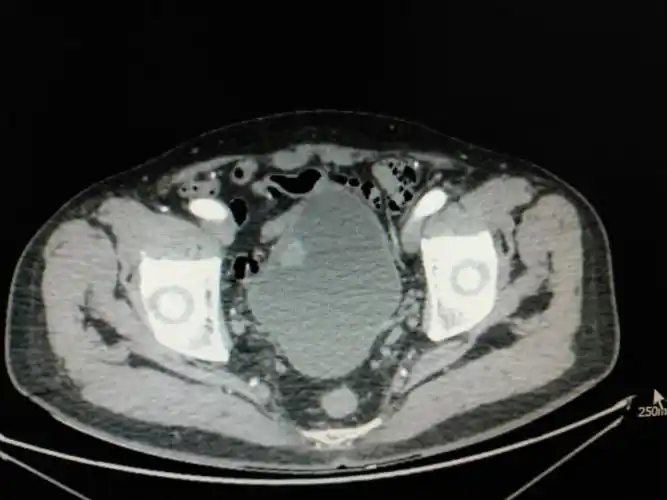

膀胱癌真实